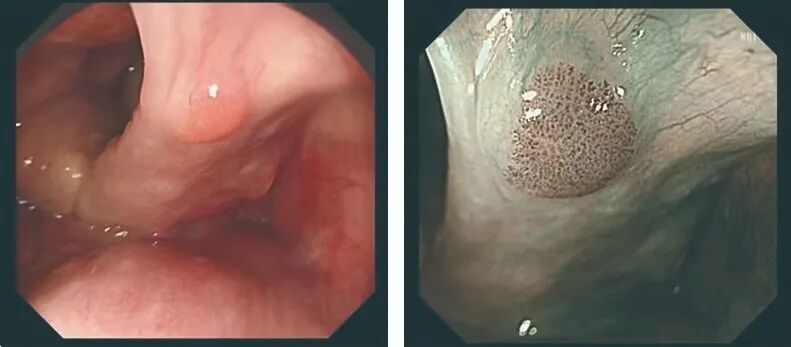

放大功能:

电子染色功能:

让早期病变无处可藏!